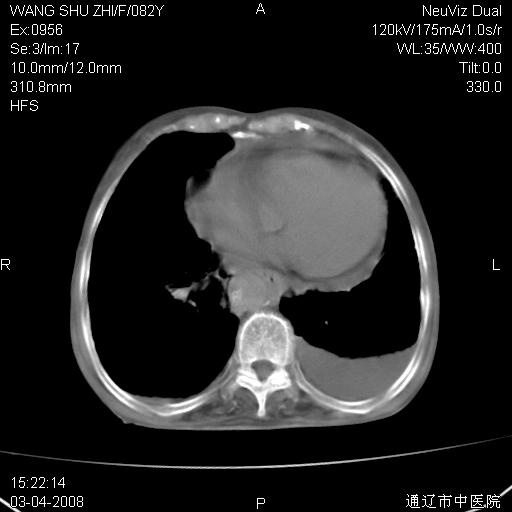

该患者为女性,82岁,既往肺心病、心衰病史。上纵隔影增宽,是否为畸形扩张的血管呢?因该患者年龄太大,又有较严重心脏病,故不适宜做增强检查。

中纵隔肿块最多见是淋巴瘤,而且以hd为多见,呈侵袭性生长,纵隔脂肪间隙消失,再加上心包和双侧胸腔积液,考虑为淋巴瘤(hd)应该说比较准确的。至于说是畸形的血管可能性小,因为畸形血管周围脂肪间隙应该存在。

纵隔淋巴结转移或淋巴瘤;双侧胸腔积液,心包积液。肺窗呢?

病史太简单,年龄太大,首先考虑转移!左侧腋窝亦见肿大淋巴结。

左侧腋窝及纵隔内见多个肿大淋巴结影,左侧少量胸腔积液,心包积液,支持淋巴瘤可能性大,不除外淋巴结转移。